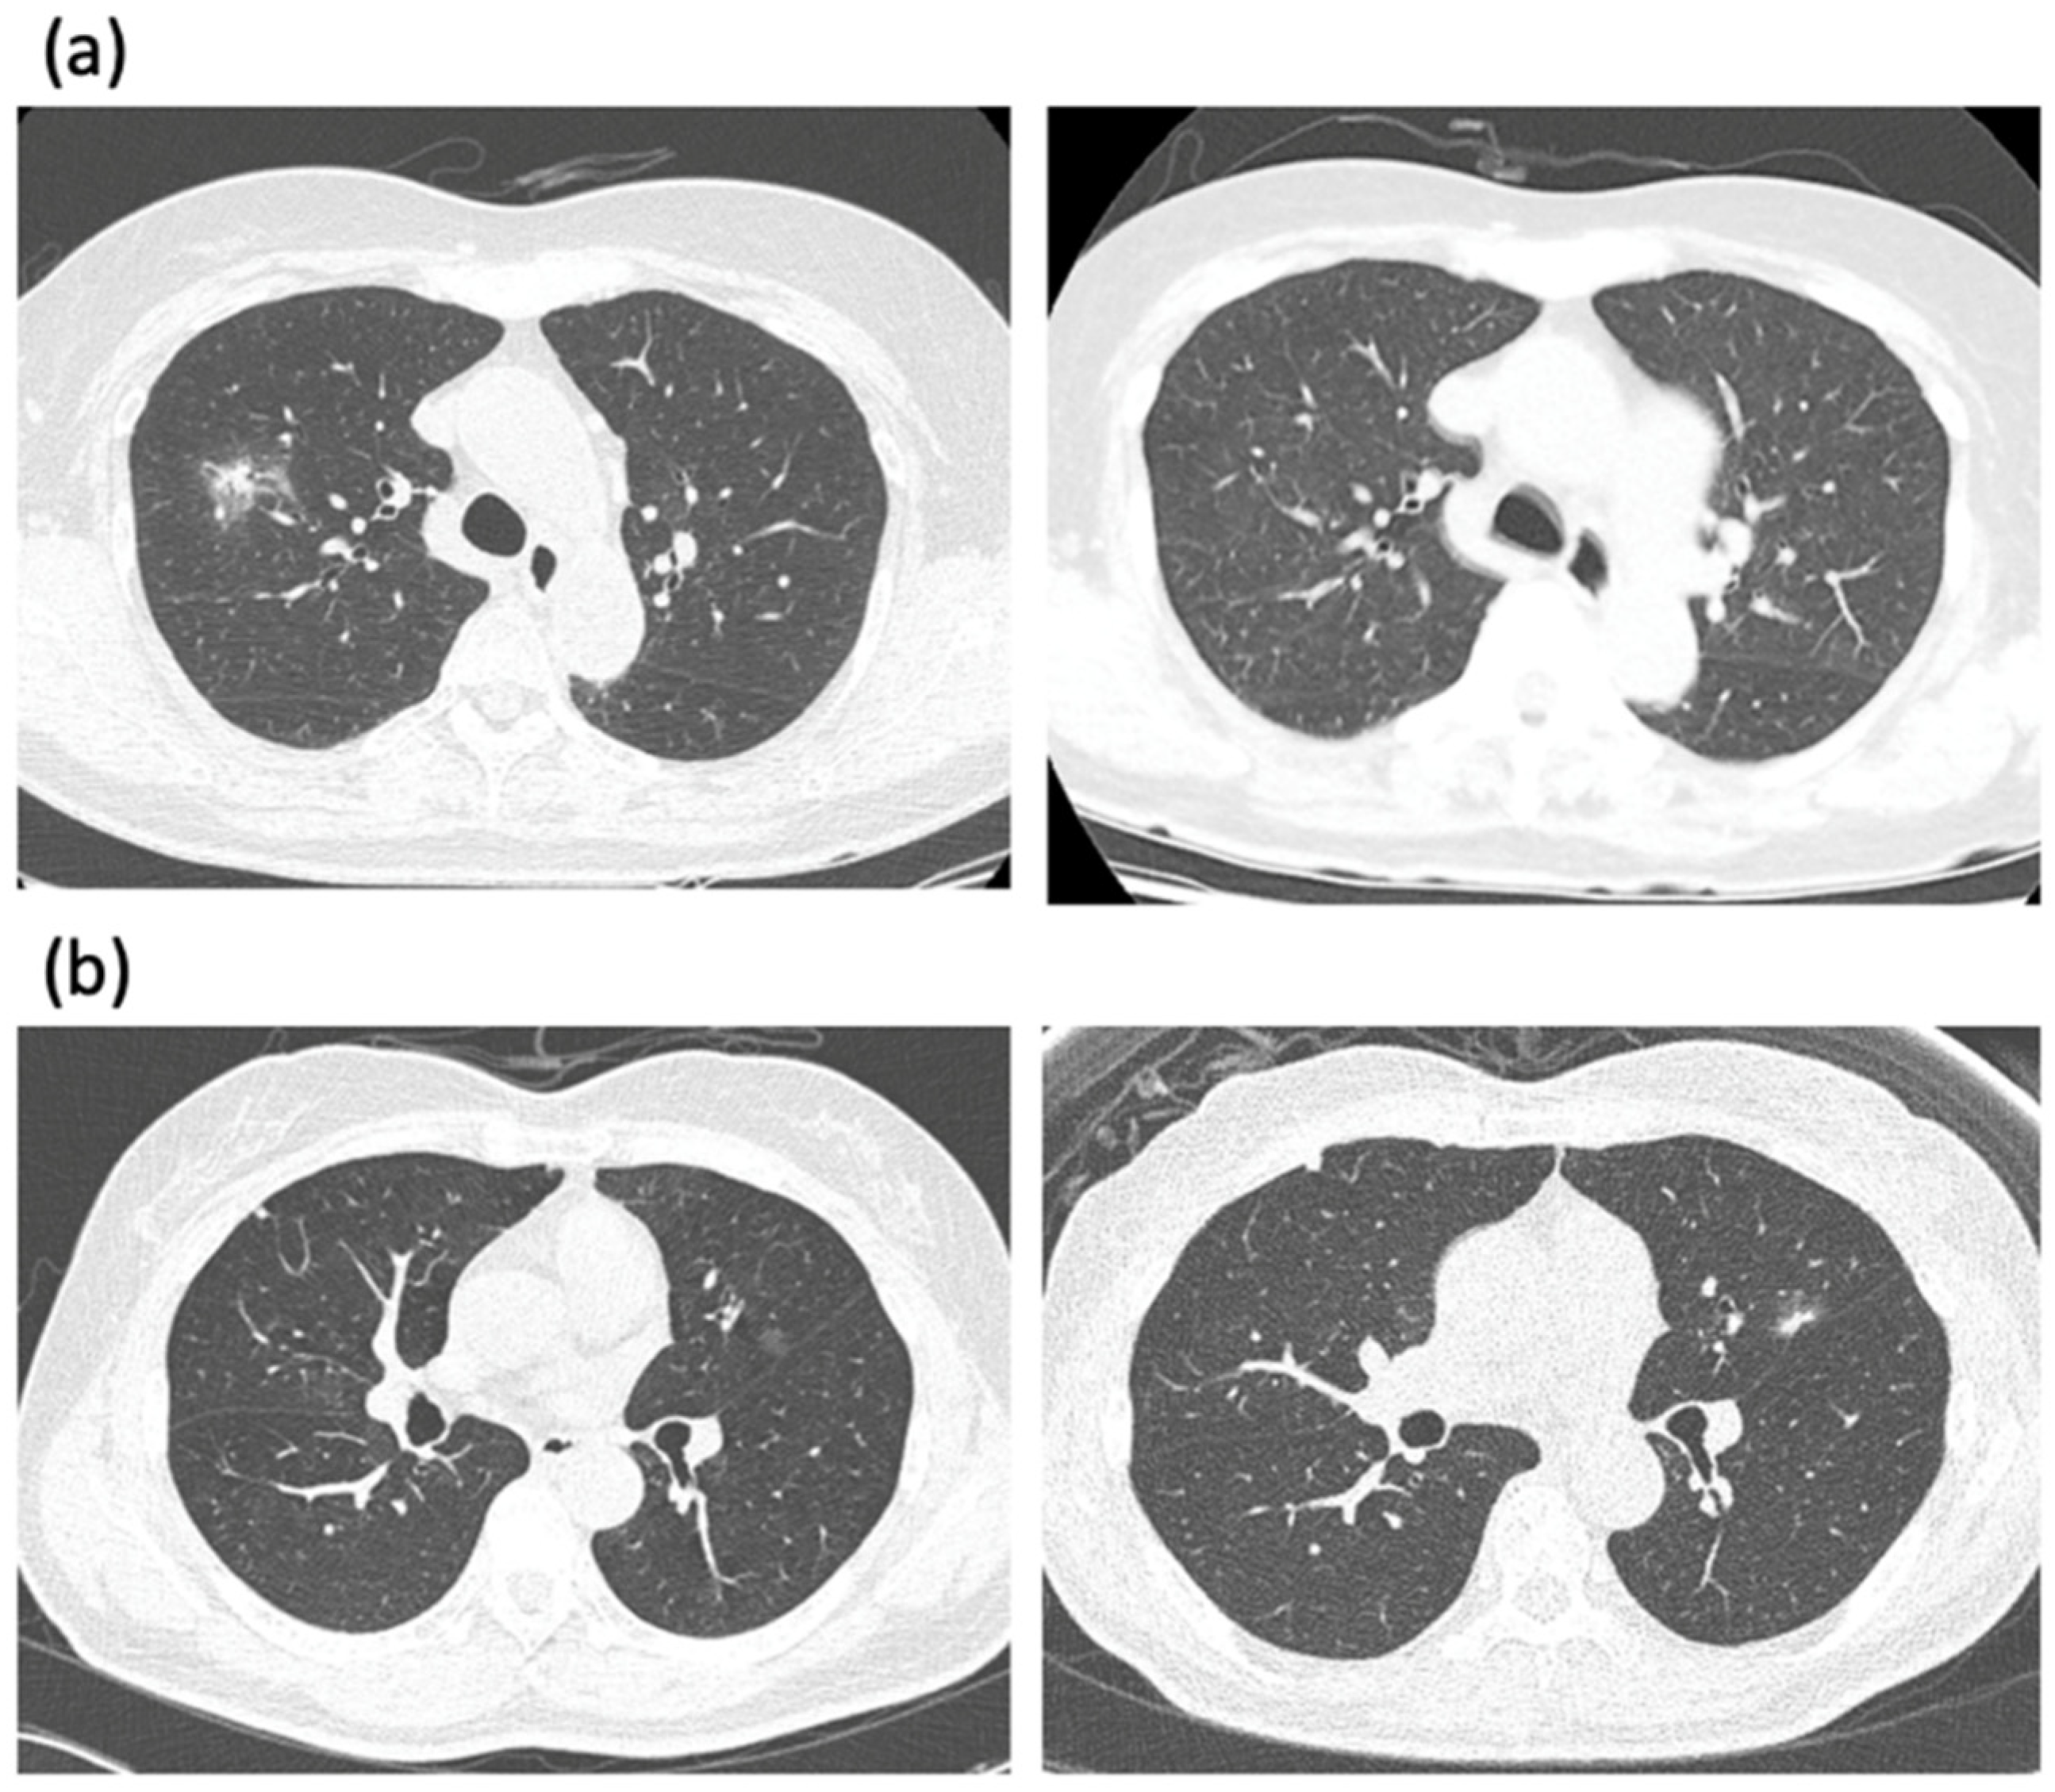

Discover the causes, symptoms, and treatments for liquid in the heart, clinically known as pericardial effusion. Learn how this condition leads to excess fluid buildup around the cardiac muscle, the risks of pericardial tamponade, and why timely medical diagnosis is essential for effective heart health management. Find expert insights on protecting your cardiovascular well-being today.